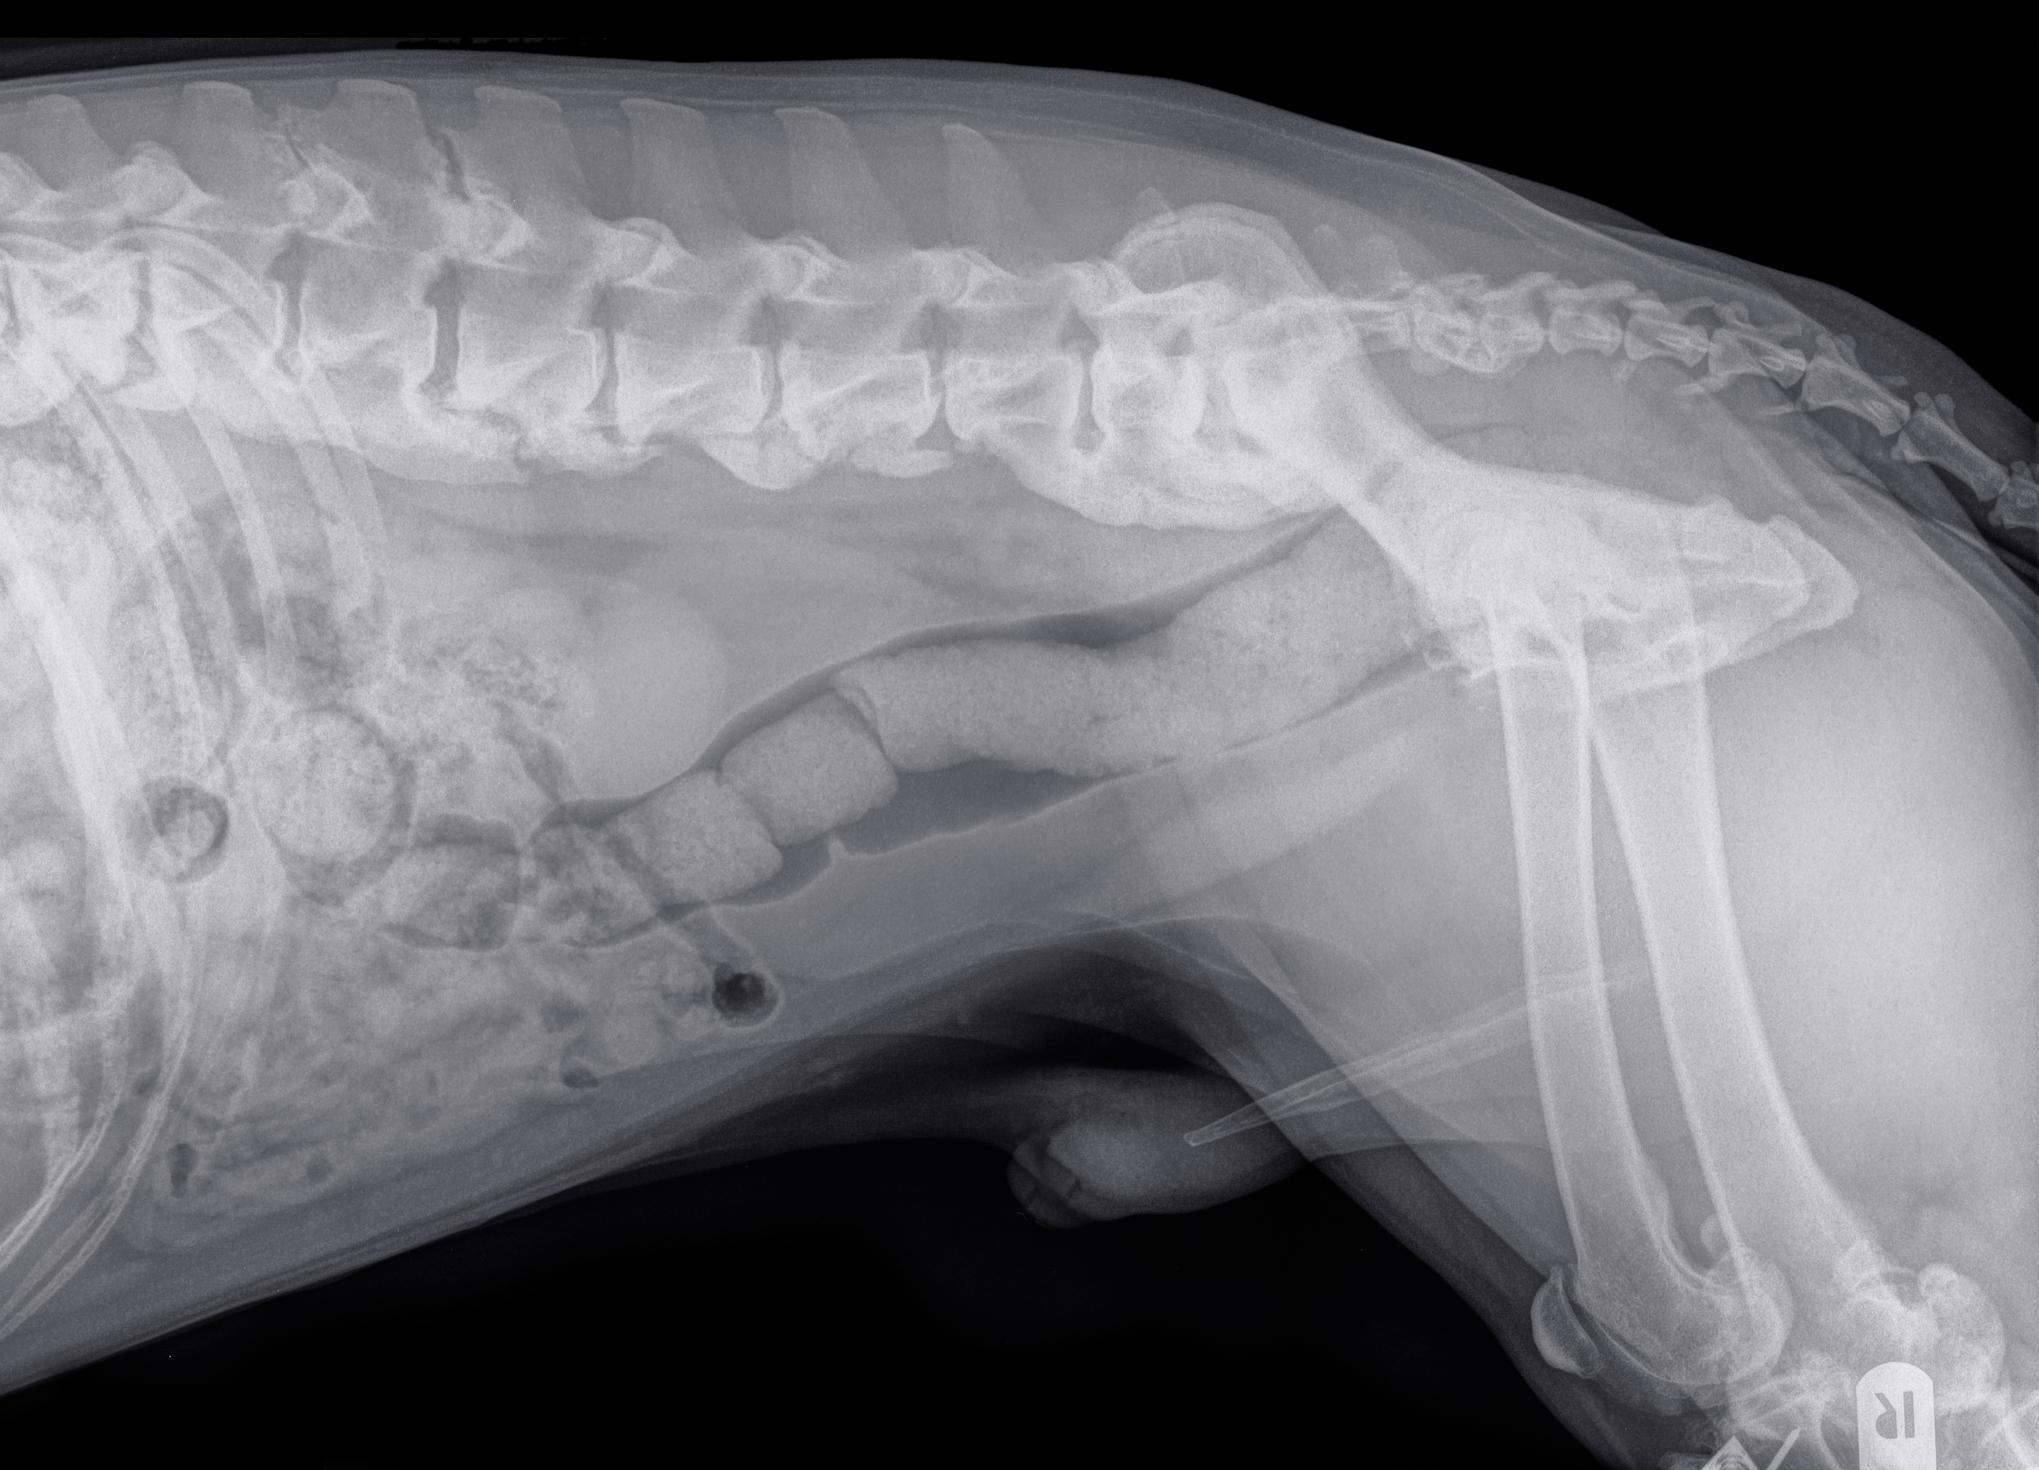

O diagnóstico de espondilose deformante canina é simples e é realizado por meio de radiografia. No entanto, é importante incluir um exame neurológico completo dentro do protocolo para poder detectar possíveis danos neurológicos produzidos pela espondilose.

No exame radiográfico, a espondilose é observada em forma de protusões (osteófitos) da borda inferior das vértebras até os extremos anterior e posterior das vértebras adjacentes. À medida que avança, adquire um aspecto em forma de gancho que comumente recebe o nome de "bico de papagaio". Nos casos mais avançados, chega a se formar uma ponte que une dois corpos vertebrais em nível ventral. Quando somente se observa um osteófito na vértebra, se pode chamar de espondiloartrose canina.

Diante deste tipo de lesão, é importante realizar um diagnóstico diferencial com outros processos que também ocorrem com a formação de osso novo, como os tumores vertebrais ou a espondilite. No entanto, um simples exame radiológico permitirá distinguir a espondilose destas outras patologias.